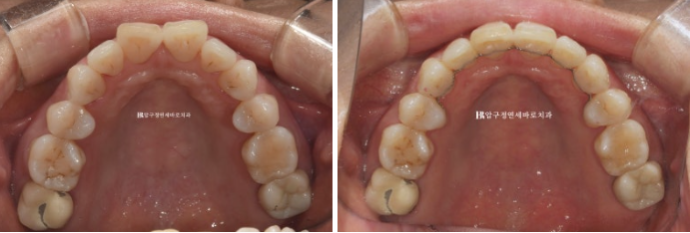

50대 환자분께서 앞니가 점점 뻗치고 틀어져서 교정을 위해 내원하셨습니다.

오래 전 발치교정이 이미 끝났는데 나이가 들면서 점점 앞니가 틀어져서 앞니 부분교정을 위해 오셨습니다.

위 앞니 두개가 튀어나와있고 회전이 되어있습니다.

정식용어는 아니지만 이런 치아를 나비치아 라고 합니다.

이 정도면 인비절라인 라이트로 충분한 교정이 가능합니다.

24.01

배열이 가지런해졌고 소량의 치간삭제를 통해 블랙트라이앵글도 줄었습니다.

단 위 앞니 높낮이 단차가 있어서 이 부분을 추가장치에서 해결하기로 했습니다.

23.07~24.05